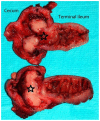

Burkitt lymphoma is a highly aggressive form of Non-Hodgkin lymphoma that responds favorably if diagnosed accurately and treated early. Recognition of the various radiologic manifestations of Burkitt lymphoma can help guide the clinician to expedite appropriate chemotherapy. We present two cases that illustrate different radiologic presentations of this aggressive gastrointestinal malignancy in children. Case 1 features a 7-year-old boy who presented to our hospital with recurrent ileocecal intussusception. Case 2 describes a 16-year-old male with history of blood-streaked stools. Ileocectomy was performed in both cases and histologic analysis showed the "starry sky pattern" and t(8;14) translocation, classic for Burkitt lymphoma. Both patients remain disease-free following surgical excision and chemotherapy.